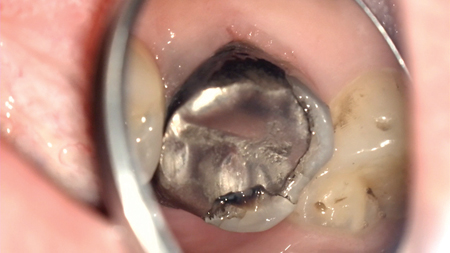

Consider very guarded endodontic and/or restorative prognosis for tooth #14

INTRODUCTION The need for endodontic care during the COVID-19 pandemic has remained as important as ever. But as we face unprecedented clinical challenges due to this ongoing pandemic, we must adjust our practice by adopting certain protocols. This article will discuss how to adapt to COVID-related considerations that centre around efficient and effective endodontic treatment … Read more